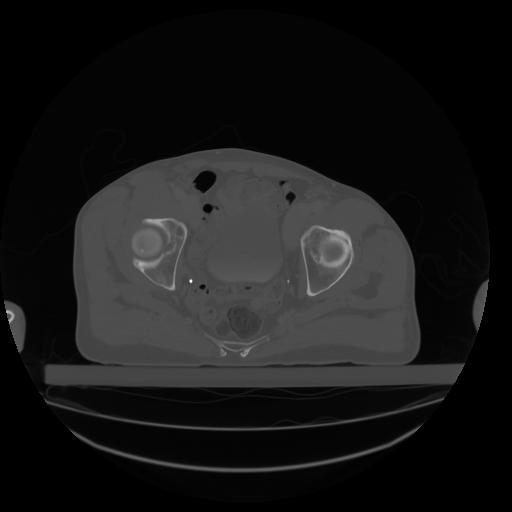

27 CUERPO,CE,Axial,3.0,CUERPO,,